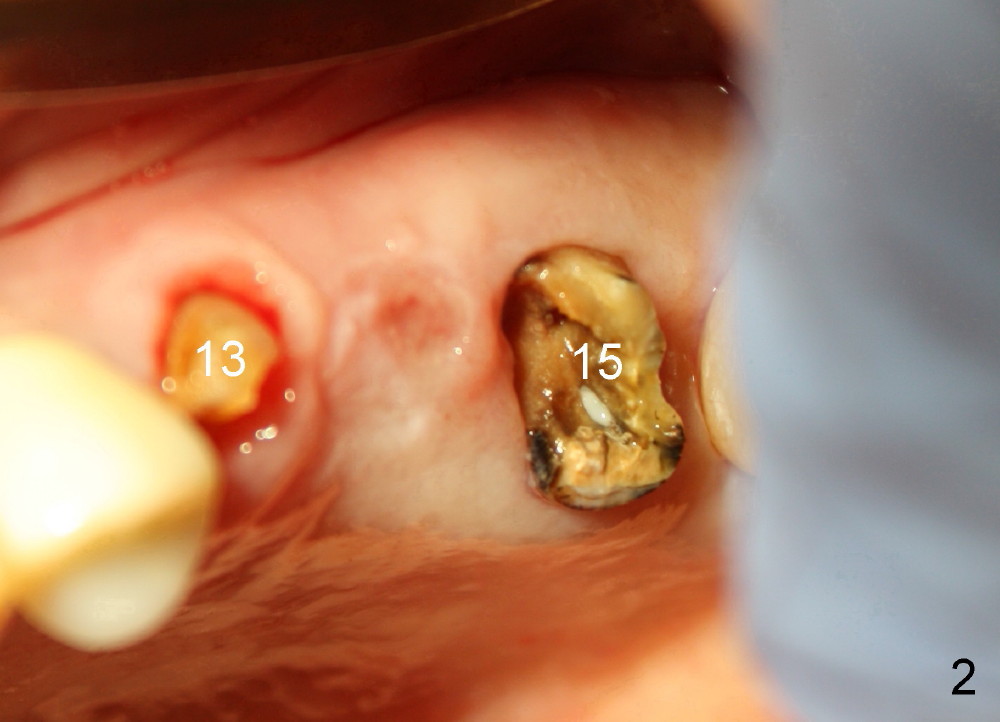

A 84-year-old man has a failing bridge.  A short implant was placed at the pontic site 5 months ago (Fig.1, taken 2 months postop).  The bridge was temporarily recemented.  It is planned at next appointment to extract #13, uncover the implant at pontic and save #15 if possible.  When the bridge is removed, the tooth #15 is also found non salvageable (Fig.2). The root stump of #15 is oval, 5x10 mm.  Preop PA shows that the 2nd molar has two roots (Fig.1: *).  When the tooth is extracted, the septum is found wide buccolingually (Fig.3: S, between the buccal (B) and palatal (P) sockets).  Osteotomy is formed in the septum with combination of drills and osteotomes, followed by insertion of taps (Fig.4).  Finally the osteotomy (Fig.5 O) in the septum (S) of #15 deviates into the buccal (B) socket.  When the implant is placed (Fig.6), it deviates buccally slightly (Fig.7).  The remaining sockets are filled by bone graft (Fig.7 G).  Immediate provisional bridge is fabricated after placement of abutments (A).  The main purpose of the provisional at early stage is to hold bone graft in place.  There is no occlusal contact with the opposing dentition,  Due to time constraint, the uncovering of #14 is postponed.  The provisional dislodges 2-3 days postop.  The patient returns for recementation 5 days postop; the sockets have initially healed (Fig.8,9, as compared to Fig.7).